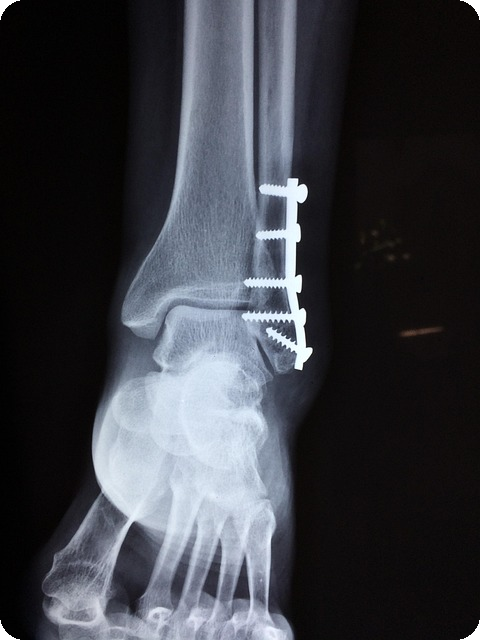

| 압박골절 | 기침이나 재채기로도 갈비뼈가 부러지는 경우가 발생합니다. |

| 고관절 골절 | 낙상 시 치명적인 골절 위험이 증가합니다. |

| 손목골절 | 넘어질 때 팔을 이용하여 바닥을 짚으면서 발생할 수 있습니다. |

이러한 진행된 증상은 일상생활에 심각한 영향을 미치게 되어, 자립적인 생활이 어려워질 수 있습니다. 특히, 고관절 골절은 회복에 오랜 시간이 걸리며, 삶의 질에 지대한 영향을 미치게 됩니다.